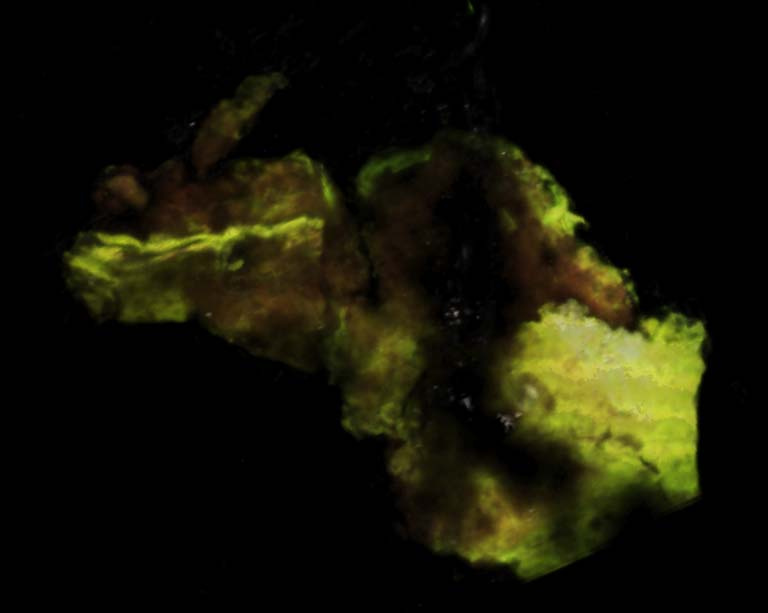

"We know now that tumors are not comprised of one type of cancer cell, rather, cancers are made of multiple types of cancer cells with different biological properties. This image represents a tumor comprised of aggressive and non-aggressive cancer cell populations. The green cells represent the aggressive cancer cells that surround the tumor mass. The less aggressive red cells are contained within. We took this image to understand how aggressive and non-aggressive cancer cells interact with each other within a tumor. This is important for developing more effective and targeted therapies for cancer patients."